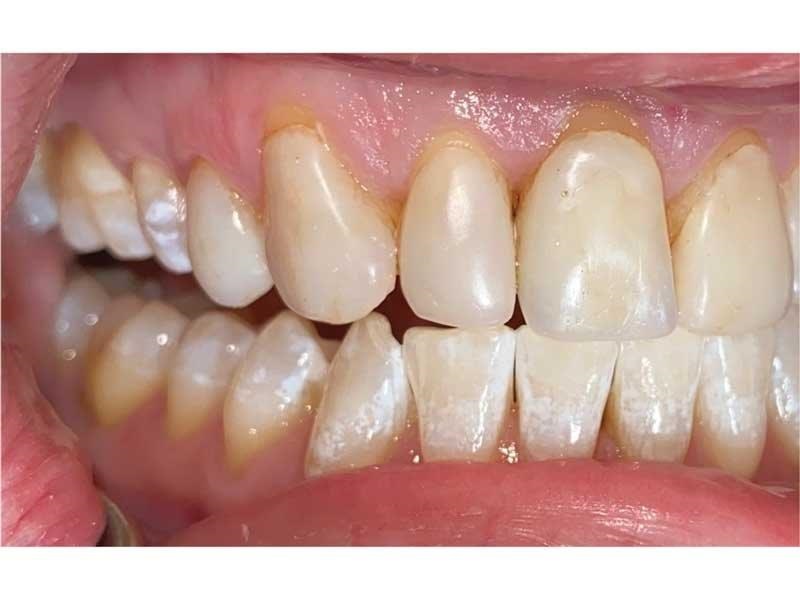

Meet Lorraine, who came into my office to “redo her bonding.” Lorraine had some upper anterior teeth done years ago with resin, which now was dull, stained and breaking down (Figs. 1–3). She had an amount of money in mind that she thought it would cost. She was very wrong.

Fig. 1

Fig. 2

Fig. 3